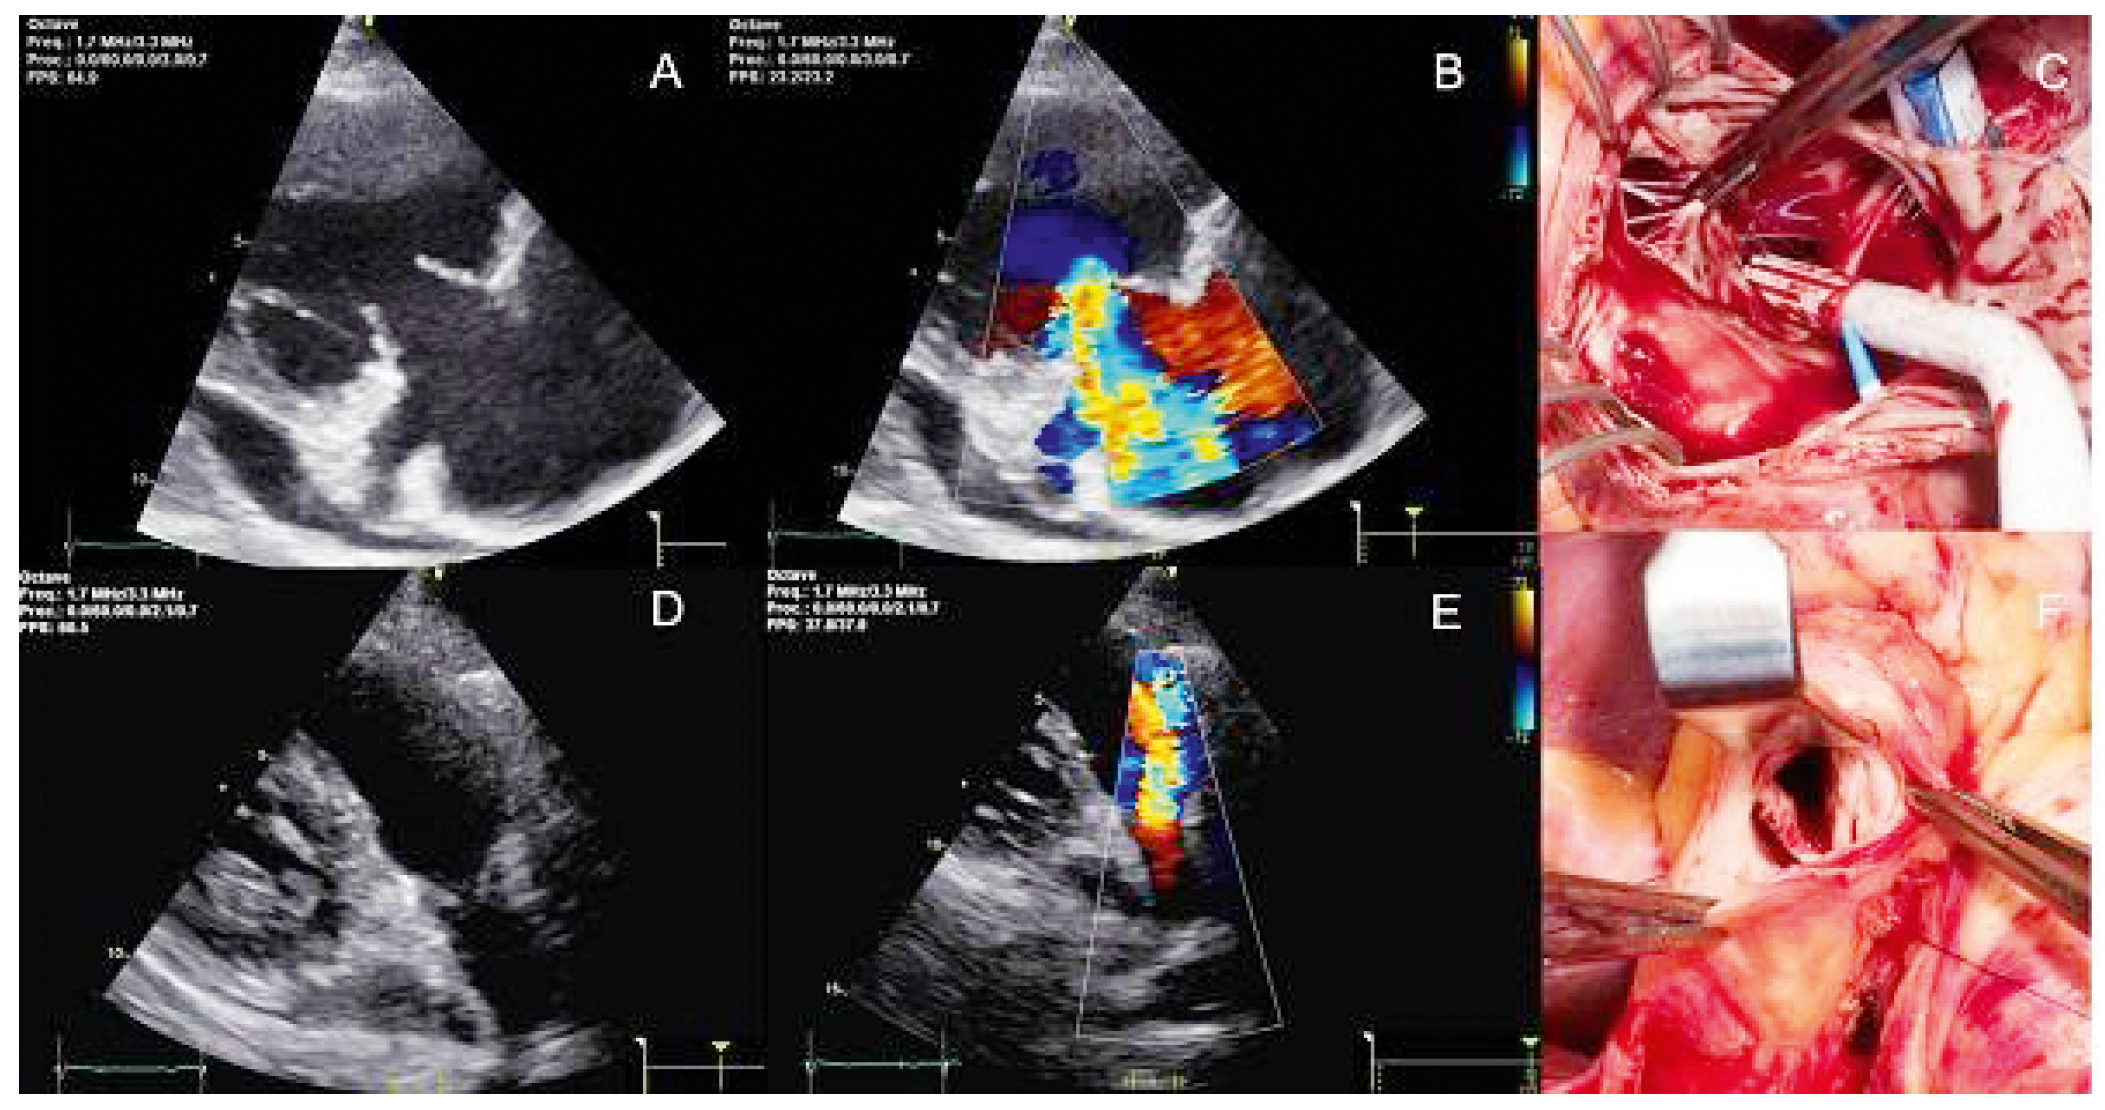

O16—Successful aortic valve repair by modified Ozaki procedure 2 years after arterial switch operation

Introduction: First described by Jatene in 1975, the arterial switch operation (ASO) has become the treatment of choice for transposition of great arteries (TGA). Neo aortic valve regurgitation (NeoAR) after ASO is a documented complication with progressive augmentation by the time in last long-term follow-up studies. We want to present a case report of a successful aortic valve reconstruction by modified Ozaki procedure 2 years after ASO.

Methods: A boy at the age of two years and 5 months was referred to our hospital because of the presence of a severe aortic regurgitation (AR) associated with sub-aortic membrane. Two years ago, at the age of 5 months, he was operated in another centre for ASO and VSD closure for d- transposition of great arteries (D-TGA) with ventricular septal defect (VSD). Echocardiography (Figure 1) showed a thickened aortic neo-valve with severe eccentric regurgitation with diastolic reflux of the descending aorta. A cardiac CT was performed and showed very tortuous thoracic aorta and discreet stretching of the pulmonary arteries with a mass aspect due to the LeCompte maneuver. The thoracic aorta appearing “crushed” by the LeCompte maneuver.

Results: Redo sternotomy was performed, the heart and great vessels were dissected and exposed. Under the CPB, neo-pulmonary root was transected (pulmonary root was on anterior after the LeCompte maneuver), aorta was clamped and selective cardioplegia was administrated. We note a retracted and shortened anterior leaflet caused by VSD patch. Other two leaflets were normal. After the resection of the anterior leaflet and sub-aortic membrane, we started the aortic valve reconstruction. The distance between commissures was measured with special Ozaki sizing device. Because of the missing of the autologous pericardium, we used a CardioCel® patch (bovine pericardium). The size corresponding to the measured value was cut. The annular margin of the patch leaflet was sutured with 5-0 Prolen running sutures to the annulus. Commissural coaptation was secured with additional 5-0 Prolen sutures. The aortotomy was closed. Intraoperative echocardiography showed an excellent result.

Conclusions: Use of aortic valve repair technique proposed by Ozaki and colleges helped us to repair the NeoAV. This technique could be an alternative technique for repair of the NeoAV after the ASO, especially in patients with small aortic root which is not large enough to implant mechanical or biological prosthesis.